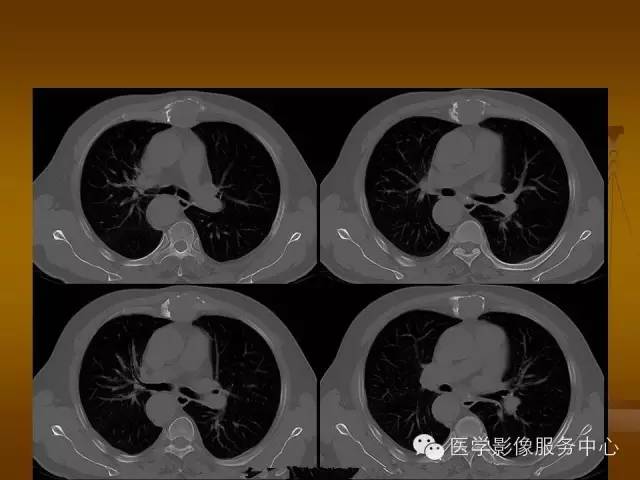

胸骨浆细胞骨髓瘤1例CT影像表现

特征性穿凿状、鼠咬状及蜂窝状骨质破坏,边缘清楚,骨质疏松,病理性骨折及软组织肿块等表现,骨质硬化及骨膜反应少见。

骨质破坏区完全为软组织取代,骨质膨胀,边界清楚,常突破骨皮质形成软组织肿块。

1、 软骨瘤:胸骨很常见,其在CT上表现为环状或分房状膨胀性生长,骨皮质完整,不侵犯邻近组织,软骨瘤可发生恶变。